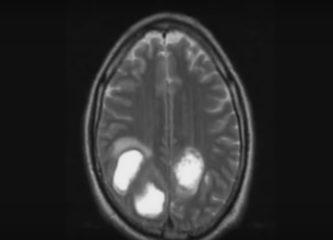

Опухоль

Онкология

Опухоль мозга — какие симптомы должны насторожить?